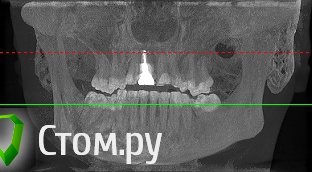

sergey765 Опубликовано 11 июня, 2014 Автор Поделиться Опубликовано 11 июня, 2014 посмотрите пожалуйста КТ. Ссылка на комментарий

sergey765 Опубликовано 11 июня, 2014 Автор Поделиться Опубликовано 11 июня, 2014 могу вам ещё снимков выложить.их довига. беспокаят меня боли после удаления .прошло 5 недель. снимки девушка лет 20 эти смотрела. сказала что у меня там инфекции дофига. типа давай я тебя на понедельник к хирургу запишу. он ранку вскроет. прочистит Ссылка на комментарий

Bier Опубликовано 11 июня, 2014 Поделиться Опубликовано 11 июня, 2014 это все не информативные кадры, в прикрепленных темах есть инструкция, выкладывайте КТ целиком, наш рентгенолог скачает и выложит срезы. 3 Ссылка на комментарий

sergey765 Опубликовано 12 июня, 2014 Автор Поделиться Опубликовано 12 июня, 2014 хорошо сейчас скидываю весь диск в рар архиве в файлообменник. люди добрые пожалуйста скачайте посмотрите. умоляю на коленях. ситуация у меня крайне серьезная. мне нужно чтобы хороший хирург посмотрел. в долгу не останусь. и если что у меня сильно там серьезное приеду к вам в клинику в москву/питер. а там что-то полюбас будет..... вчера когда делал КТ в частной клинике девочка (лет 20) смотрела, нифига вроде не поняла, сказала только у меня там инфекции полно (где там я не понял) и лунка удаленного зуба не заживает типа надо хирургу показать он вскроет прочистит т.е возможно когда мне зуб удаляли не прочистили там ничего... сейчас меня беспокоят боли в районе подбородка. самочувствие моё плохое. с кровати почти не встаю. все написано в начале данной темы.умоляю скачайте посмотрите. томограмма сделана программой iCATVision Ссылка на комментарий